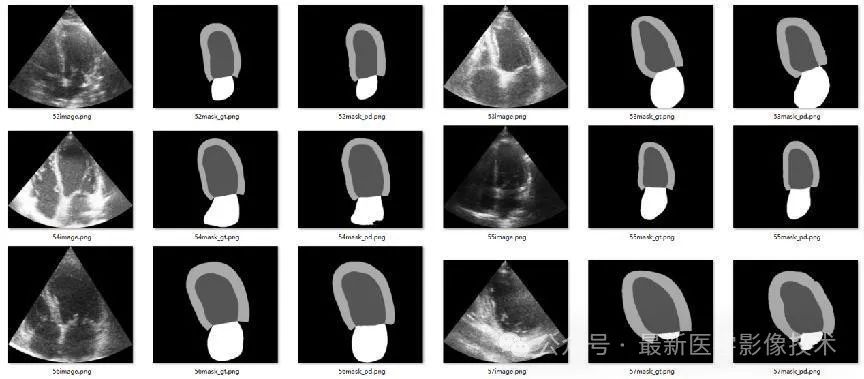

4、验证集部分分割结果